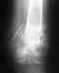

В октябре 2005 года попала в ДТП. В результате почти месяц пролежала в коме. Мой диагноз:ЗЧМТ, ушиб головного мозга, перелом поперченых отростков Л4,Л5 слева, перелом крыла подвздошной кости, лонной, седалищной костей справа со смещением отломков, перелом боковой массы крестца слева, открытый оскольчатый перелом левого бедра со смещением, закрытый фрагментарный перелом костей правой голени со смещением отломков, Диафизарный перелом лучевой кости правого предплечья со смещением.Шок 2-3 степени.Мне 24 года, сейчас я хожу в аппарате Илизарова на левом бедре и правой голени. Гипс с руки и Илизарова с таза уже сняли. Хотелось бы узнать какие последствия после такой травмы в плане моего здоровья меня ждут? Невропатолог говорит, что года через 2 я приду в норму (сейчас у меня пониженное давление).

Более-менее определенный прогноз по столь скудной информации, без снимков, дать невозможно. В принципе диапазон от практически полного восстановления до стойкой инвалидности. Это зависит от восстановления формы тазового кольца, длины, оси и ротации костей конечностей, срока фиксации в аппаратах, степени восстановления движений в суставах.